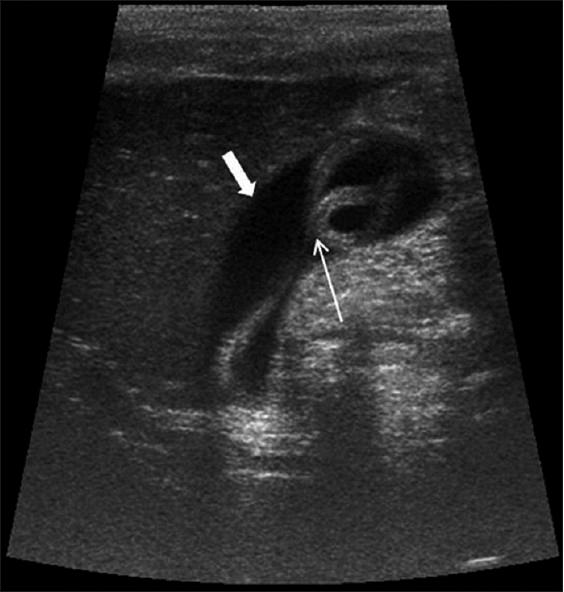

Klatskin Tumor

malignant tumor arising between the left and right hepatic ducts